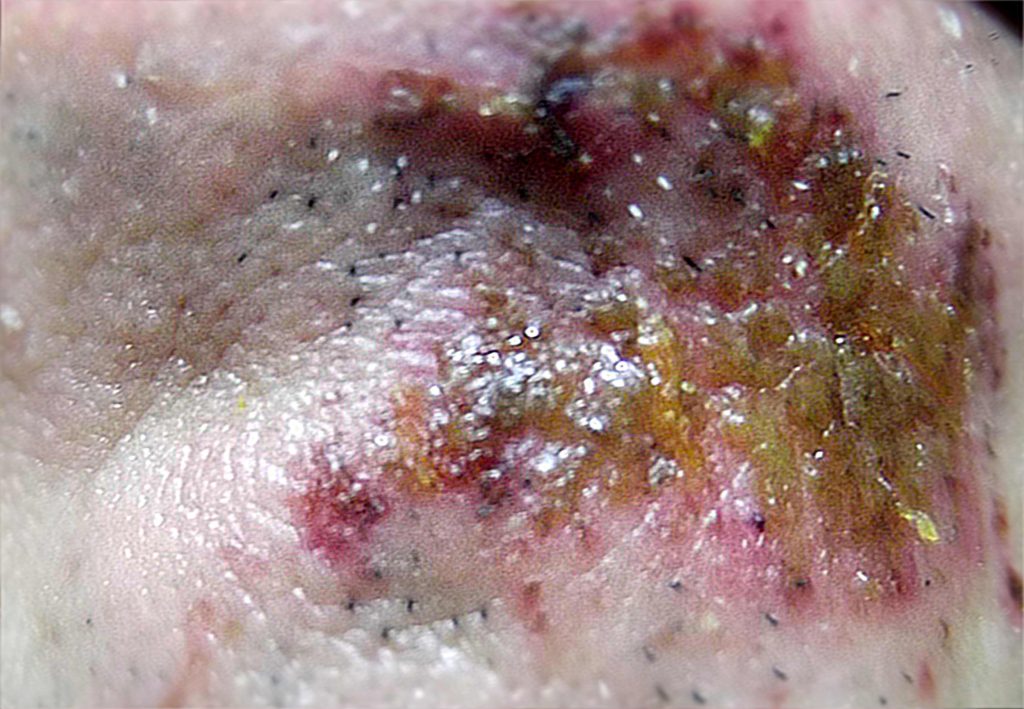

今回は結局は整形外科での精密検査に及ぶレベルの負傷=怪我となりました。

今回のダメージは経験則から観て

自分にとっては割と高度な部類となりました。

X線は10数枚以上に達しました。

現時点では,"顎関節症"と呼ばれる,左耳がくしゃくしゃと話したり食事する度うるさくてしかたがありません!

顎(あご)の左側の関節部が少しずれているのではと思いますが,

相手の外力によって顎の左側に問題は起きていると判断していますが

手の外皮の怪我の程度はさして

"高度"ではありませんでした。

私の今回の"手"の甲は2週間もすれば"完治"する程度でした。

※後述:形成外科医からの指摘要素では

私の左側と右側の”裏拳"の外傷が著しく違うとの指摘。自分は渦中,

急所,つまり"首の頸動脈や金的,心臓部,垂直打法に依る1本拳,目突きを本能的に避けた

ことから相手の左右の"脇腹"を打ったが,左右,甲の怪我の仕方が違う事を医者から指摘された。

これはおそらく相手(左側の影の脇腹を打った際,服や,もしくは服の

装飾品,服に付帯していた金属部(例えば移動体端末通信機器)などに当り,

怪我の仕方が変ったのだろうと担当整形外科医の判断となった。

なんとか帰ってきて,負傷した左の膝を観たところ,やはり膝の皿の外皮がかなり損傷し,血に染まっていました。

"皿の骨"が露出しているのではと見当していましたが,外傷は"高度"ではありませんでした。問題は内部でした。

2.3枚目は顎の怪我で2日目と翌日の3日目(化膿してきたかな)といった画像です。自分が観ても本当に"気持ち悪い画像"ですので,クリックして,あまり観ない方が宜しいかと思います。